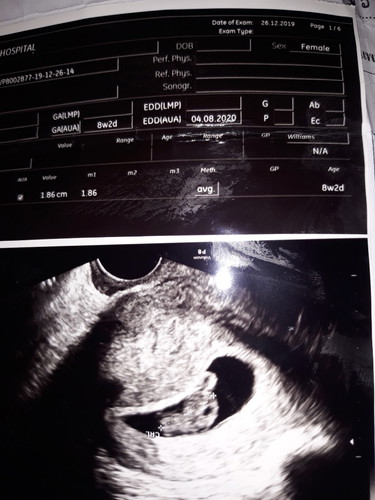

นี่ค่ะ หรอไม่ก็ดูในสมุดฝากครรภ์ที่หมอเขียนให้ค่ะ

4/8/2020